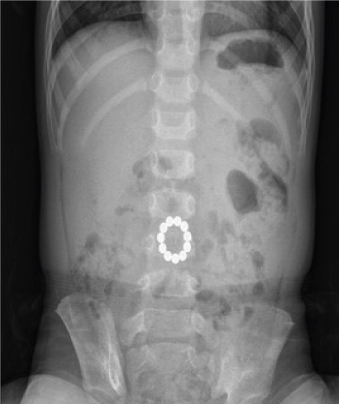

A 19-month-old girl presented with abdominal pain and mild fever for 3 days. She had been treated at another clinic, and foreign bodies were accidentally found on abdominal radiography because her parents had not seen her ingesting the magnets. Abdominal radiography revealed 9 bead-shaped magnets arranged in a circle (Fig. 3). She was transferred to our institution for proper management. Her symptoms were not severe but did not improve. On physical examination, her abdomen was soft, mildly tender, and non-distended. Her C-reactive protein level at admission was elevated (35.66 mg/L), and other laboratory findings were nonspecific. She had been examined with repeated abdominal radiographies for 1 day after admission, which revealed no significant change in the position of magnets. Therefore, exploratory laparotomy was performed. Magnets were found in the stomach and proximal jejunum, approximately 5 cm distal to the Treitz ligament, adducting toward each other through the transverse mesocolon (Fig. 4). Necrotic segments of the gastric perforation site were excised, and primary closure with an omental patch was performed. Wedge resection of the jejunum, including the 2 perforation sites, was performed using a linear stapler. She had an uneventful postoperative recovery course and was discharged on the fifth postoperative day. The need for ethic approval is not subject to the institutional review board (local ethics committee) due to simple case reporting. Written informed consent was obtained from the patient's parents in both cases to report and publish individual patient data.

Fig. 3

Abdominal X-ray demonstrating 9 bead-shaped magnets in left upper abdomen.